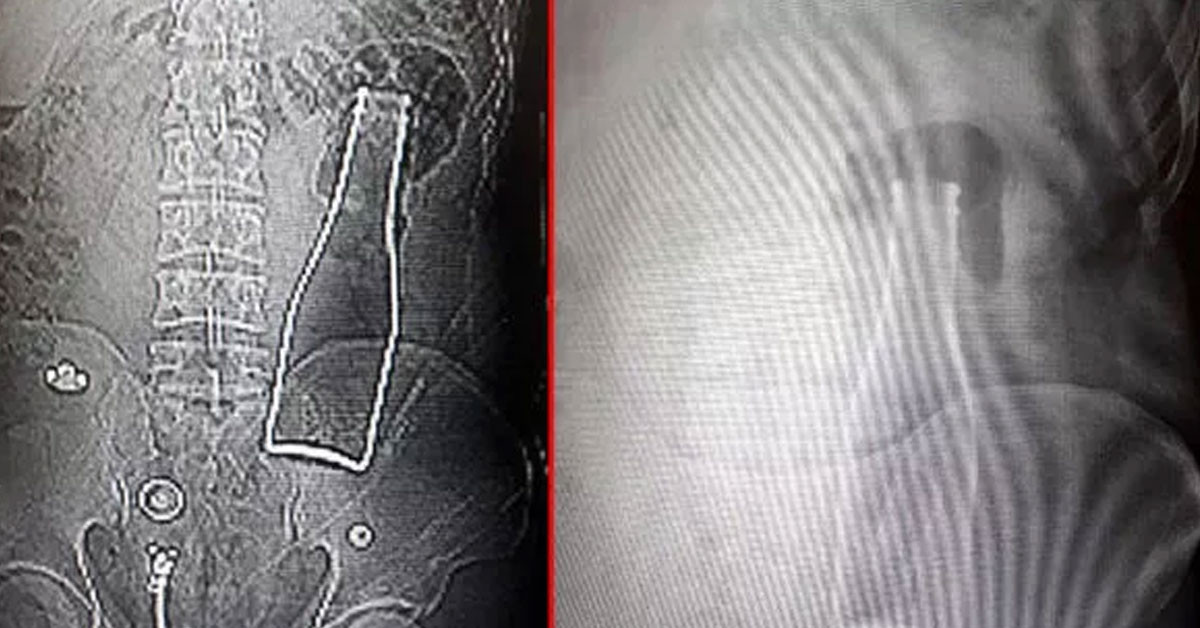

Anal bölgesine fantezi oyuncağı sokan genç kadın daha sonra oyuncağın ipini koparınca bir türlü çıkaramadı.